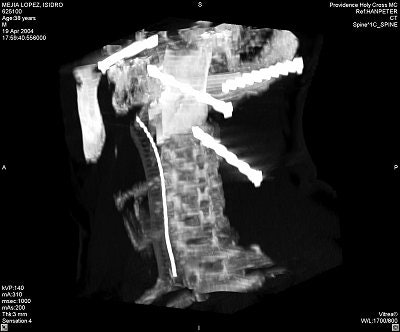

Initial x-rays showed there were six 3.5-inch nails in Mejia's head, and that his jaw bones remained intact. He immediately underwent a CT scan, with initial images showing significant metal artifact, as expected (images A-B below).

![]() |

Image A.

"Basically you could only visualize on hard-bone algorithm because of the nails," noted Greenberg. "You had very little ability to tell how much bleeding the nails had caused, and certainly you had no way to tell whether there had been injury to a specific arterial structure because there was no way to get any soft-tissue detail."

But the CT provided enough information for Quinonez to allow the patient to stabilize for a few days, when a conventional angiogram could be performed.